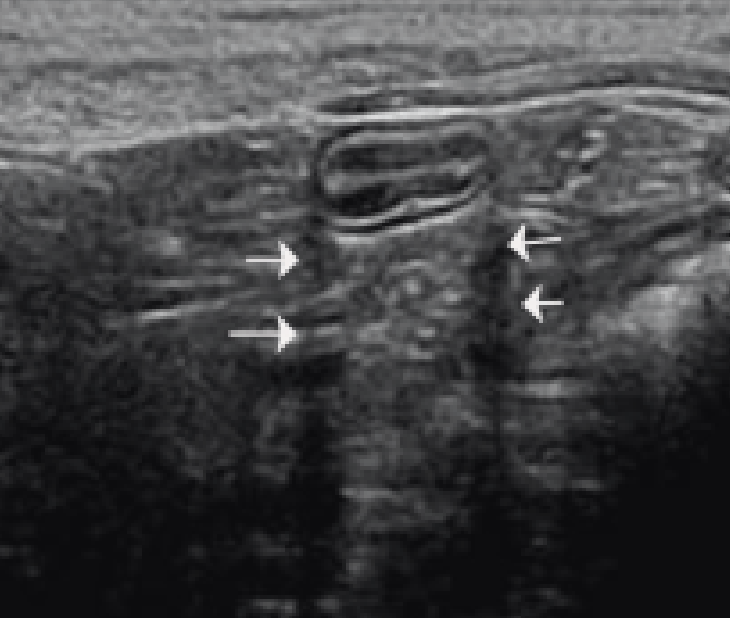

Name this artifact.

What is the cause of the artifact?

Comet tail artifact: a form of reverberation artifact with reflections occurring from two closely spaced reflective surfaces (calculi, surgical clips, etc)